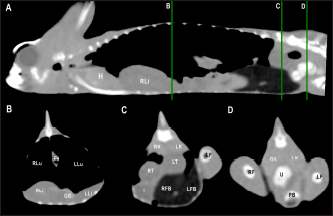

The CT examinations were performed with a 16-slice helical CT scanner (General Electric Brivo CT 385) in cranio-caudal direction with the animals positioned in ventral recumbency (Fig. 1). All studies were obtained with a slice thickness of 0.625 mm, interval thickness of 0.625 mm, collimation pitch of 0.5625:1, 120 kV, 80 mA, field of view of 20 cm and a matrix of 512 × 512. The transverse images were reconstructed in sagittal and dorsal planes using multiplanar reconstruction. CT images were displayed in a soft tissue window (window level: 350; window width: 40) and a lung window (window level: −500; window width: 1,500). Coelomic organs height and width were assessed on the transverse images and length was assessed on the sagittal and dorsal reconstructions (Fig. 2).

Fig. 2. Sagittal precontrast CT images displayed in soft tissue window (A and F) with length and height measurements of heart, liver, gallbladder, testes, kidneys, and fat bodies in a veiled chameleon (C. calyptratus). The precontrast CT transverse images displayed in soft tissue windows B–E show the width and height measurements of the same organs. H, heart; RLi, right liver lobe; LLi, left liver lobe; GB, gallbladder; RK, right kidney; LK, left kidney; RT, right testicle; LT, left testicle; RFB, right fat body; and LFB, left fat body.